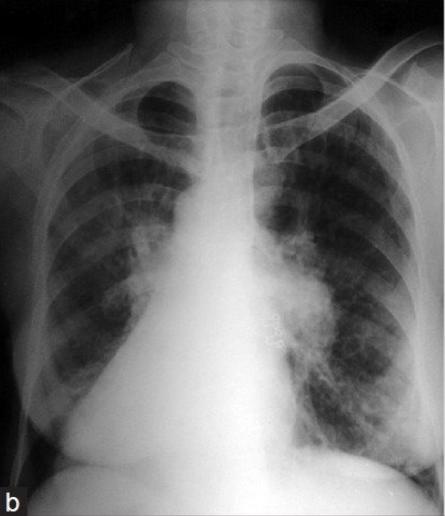

5.5 Looking at few qualitative examples

To see for what images the model is making correct predictions and for what images model is mis-classifying, we show here randomly selected few examples. Figure 6 shows sample examples of correct predictions made by the model under different experimental settings. Figure 7 shows sample examples where model fails to predict the correct class of the input image. A closer look to these examples reflect that model is doing well in distinguishing paediatric chest X-rays and adult chest X-rays because of distinguishable anatomical features. Also, model is doing correct predictions for COVID-19 cases where the severity of COVID-19 infection is high. On the other hand, model is failing for mild and moderate cases where the radiographic features of COVID-19 infection are not fully developed and not visible in chest X-rays.

Correct predictions Refer to caption (a) COVID-19 case correctly identified Refer to caption (b) Paediatric patient correctly identified Refer to caption (c) Adult patient correctly identified Refer to caption (d) Mild case of COVID-19 correctly identified Refer to caption (e) Moderate case of COVID-19 correctly identified Refer to caption (f) Severe case of COVID-19 correctly identified

Figure 6: Correct predictions by model selected randomly under different classification settings.

Wrong predictions Refer to caption (a) COVID-19 case misclassified as Normal Refer to caption (b) Paediatric case misclassified as Adult Refer to caption (c) Negative case misclassified as Normal-PCR+ Refer to caption (d) Negative case misclassified as mild COVID-19 Refer to caption (e) Mild COVID-19 case misclassified as Negative Refer to caption (f) Severe COVID-19 case misclassified as Negative

Figure 7: Wrong predictions by model selected randomly under different classification settings.